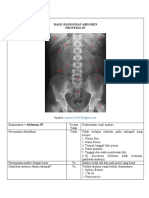

Examination = Manus YaatauTidak

Oblique

Persyaratan identifikasi Tidak Tidak terdapatID Rumah Sakit, ID pasien (nama, umur,atau punnomo

Penempatan marker dengan Ya Terdapat marker tanda L dengan orientasi benar

benar

Gambaran anatomi dalam Ya - Tampakgambaran Carpal, Metacarpal, Phalangdalamposisi Oblique

radiograf? - Tampak Caput Metacarpal 3-5 sedikit overlap,

- MCP dan Interphalangeal membuka

- Soft tissue tampak

Apakah gambaran anatomi Ya SeluruhbagianManustampak. Terlihatdari distal Phalang 1-5 sampaiP

tampak sesuai dengan

proyeksi ini?

Apakah kolimasi lapangan Ya Kolimasicukup, karenaseluruhbagian Manus sudahcukuptampak

radiasi cukup? Dan tetap

mengindahkan ALARA

(limitasi, justifikasi,

optimasi)?

Proteksi radiasi, presentasi, Tidak Tidakterdapatalatproteksiradiasi yang digunakan

menghalangi gambaran

obyek?

Garis tepi luar kortek tulang, Ya Untuktepiluarkortektulangterlihat,trabekulaterlihat, danuntuk soft tis

patren trabekula tulang, dan

atau struktur soft tissue

terlihat tajam?

Radiograf terlihat tanpa Ya Tidakterlihatkekaburangambaranradiograf

distorsi?

Ukuran film benar, regio Ya Ukuran film yang digunakansesuaidanpenempatanobjeksesuai

organ anatomi terlihat sesuai

dan benar?

Menggunakan alat Ya Ukurankasetdan film yang digunakansesuai

penerima gambar yang

sesuai?

Kecukupan daya penetrasi Ya FaktorekspositepatdapatmenampakkanPhalang, Metacarpal, Carpal 1

sinar dengan kerapatan?

Kecukupan kontras gambar? Ya Dapatdibedakanantaragambarantulangdan soft tissue

Upaya pencegahan terhadap Ya Tidak terlihatartefak yang dapatmengganggugambaranradiograf

artefak gambar?

Outcome yang dikehendaki Ya Tampakanatomi yang sesuaiproyeksi, region of interest tepat dan terl

(contoh; pemakaian sinar-

xdapat memperlihatkan nilai

diagnostik dari regio organ

anatomi)?

Kesimpulan Radiograf ini

adalah :

DITERIMA/ACCEPTED

DITOLAK/REJECTED  Tidakterdapat ID RumahSakit, ID pasien, walau pun p

tercantumsangatsulituntukmenemukanidentitaspemilikfototersebut

Jika ditolak/rejected apa Pemberian

upaya yang sebaiknya pasiensertaRumahSakitseharusnyasangatdiperhatikansehinggamemu

dilakukan dengan cara yang lain untukmenegakkandiagnosa

berbeda untuk

memperbaikiketidaksesuaian

teknik yang telah dilakukan